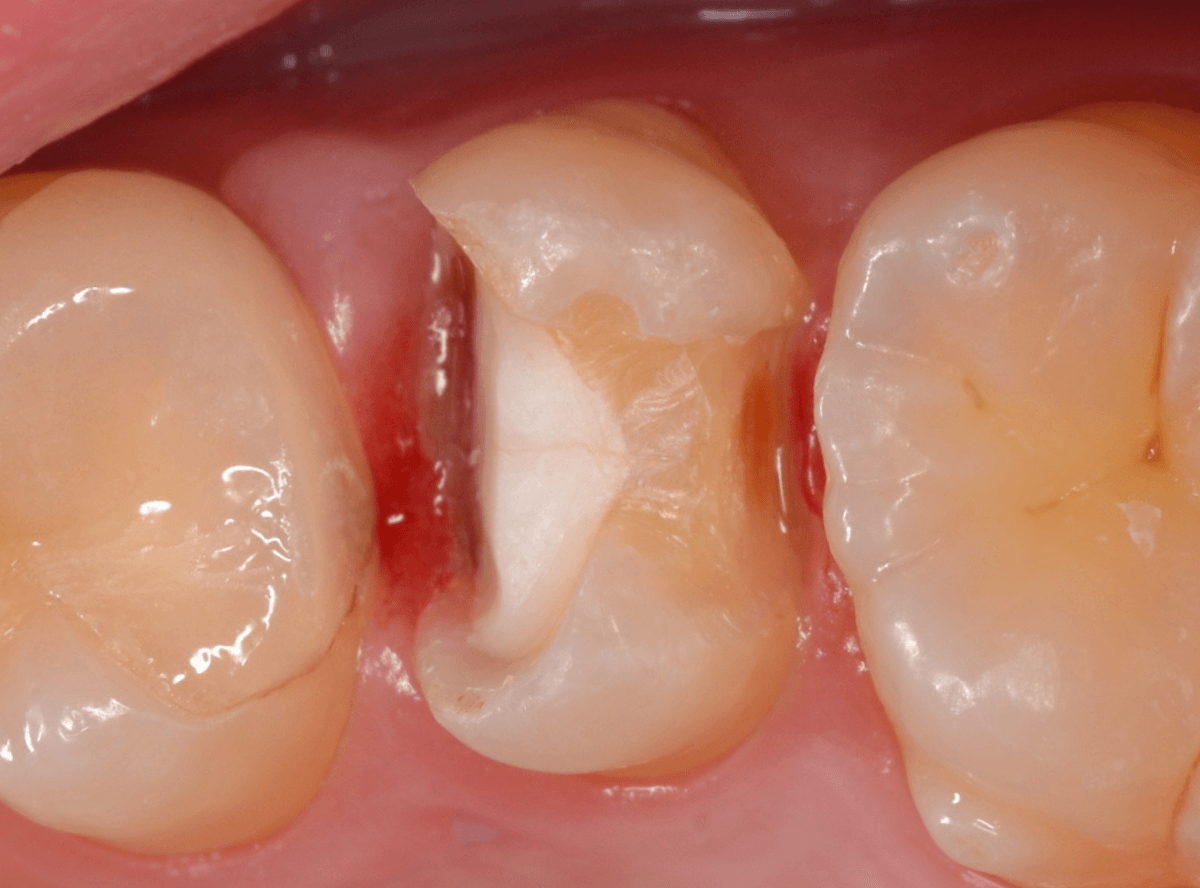

虫歯の治療を開始します。

隣の歯とのすき間を中心に広い虫歯になっていました。

虫歯治療後、特に症状もなく経過観察できましたので、つめものを作る治療に入ります。

セラミック治療をご希望されましたので、

小臼歯をE-MAX・インレー、

大臼歯をジルコニア・インレーで処置することになりました。